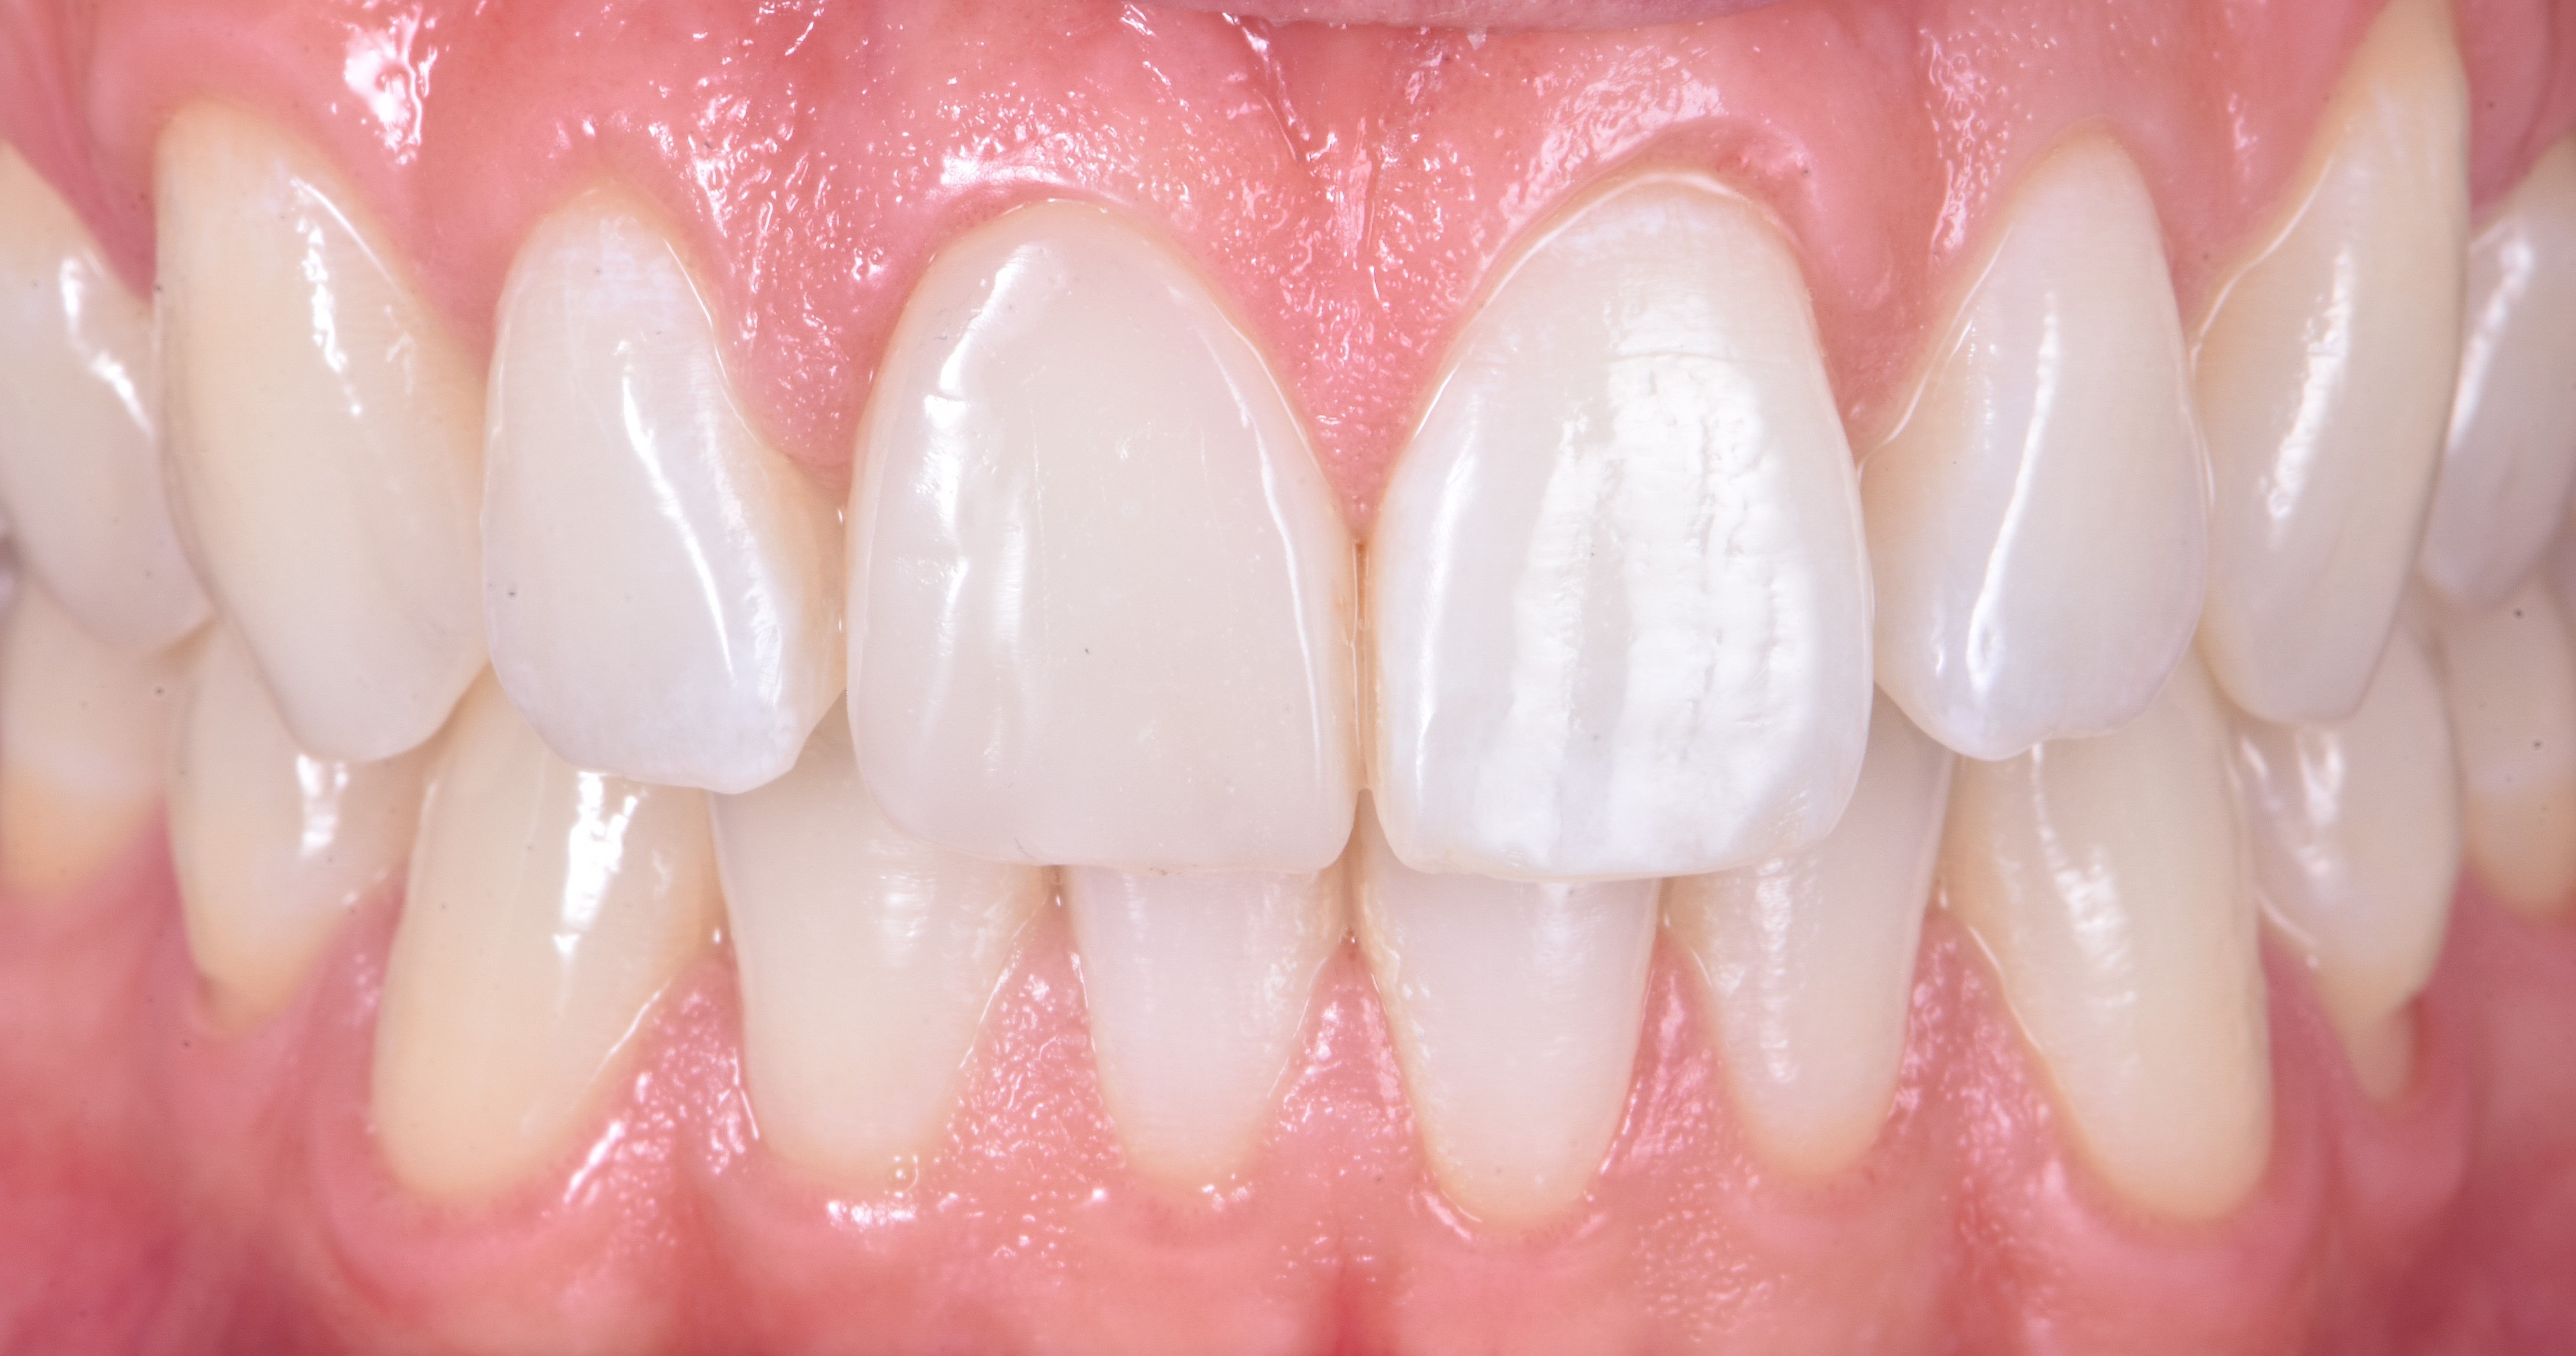

30-letni pacjent bez istotnego wywiadu medycznego zgłosił się w celu wymiany rekonstrukcji kompozytowej wykonanej przed 10 laty po doznanym wówczas urazie zęba 11. Ząb ten w badaniu klinicznym reagował na test żywotności i nie wykazywał zmian okołowierzchołkowych na zdjęciu rentgenowskim wykonanym w dniu badania (ryc. 1).

Korona zęba 11 była przebarwiona i ustawiona bardziej podniebiennie w porównaniu z koroną zęba sąsiedniego, tj. zęba 21 (ryc. 2).